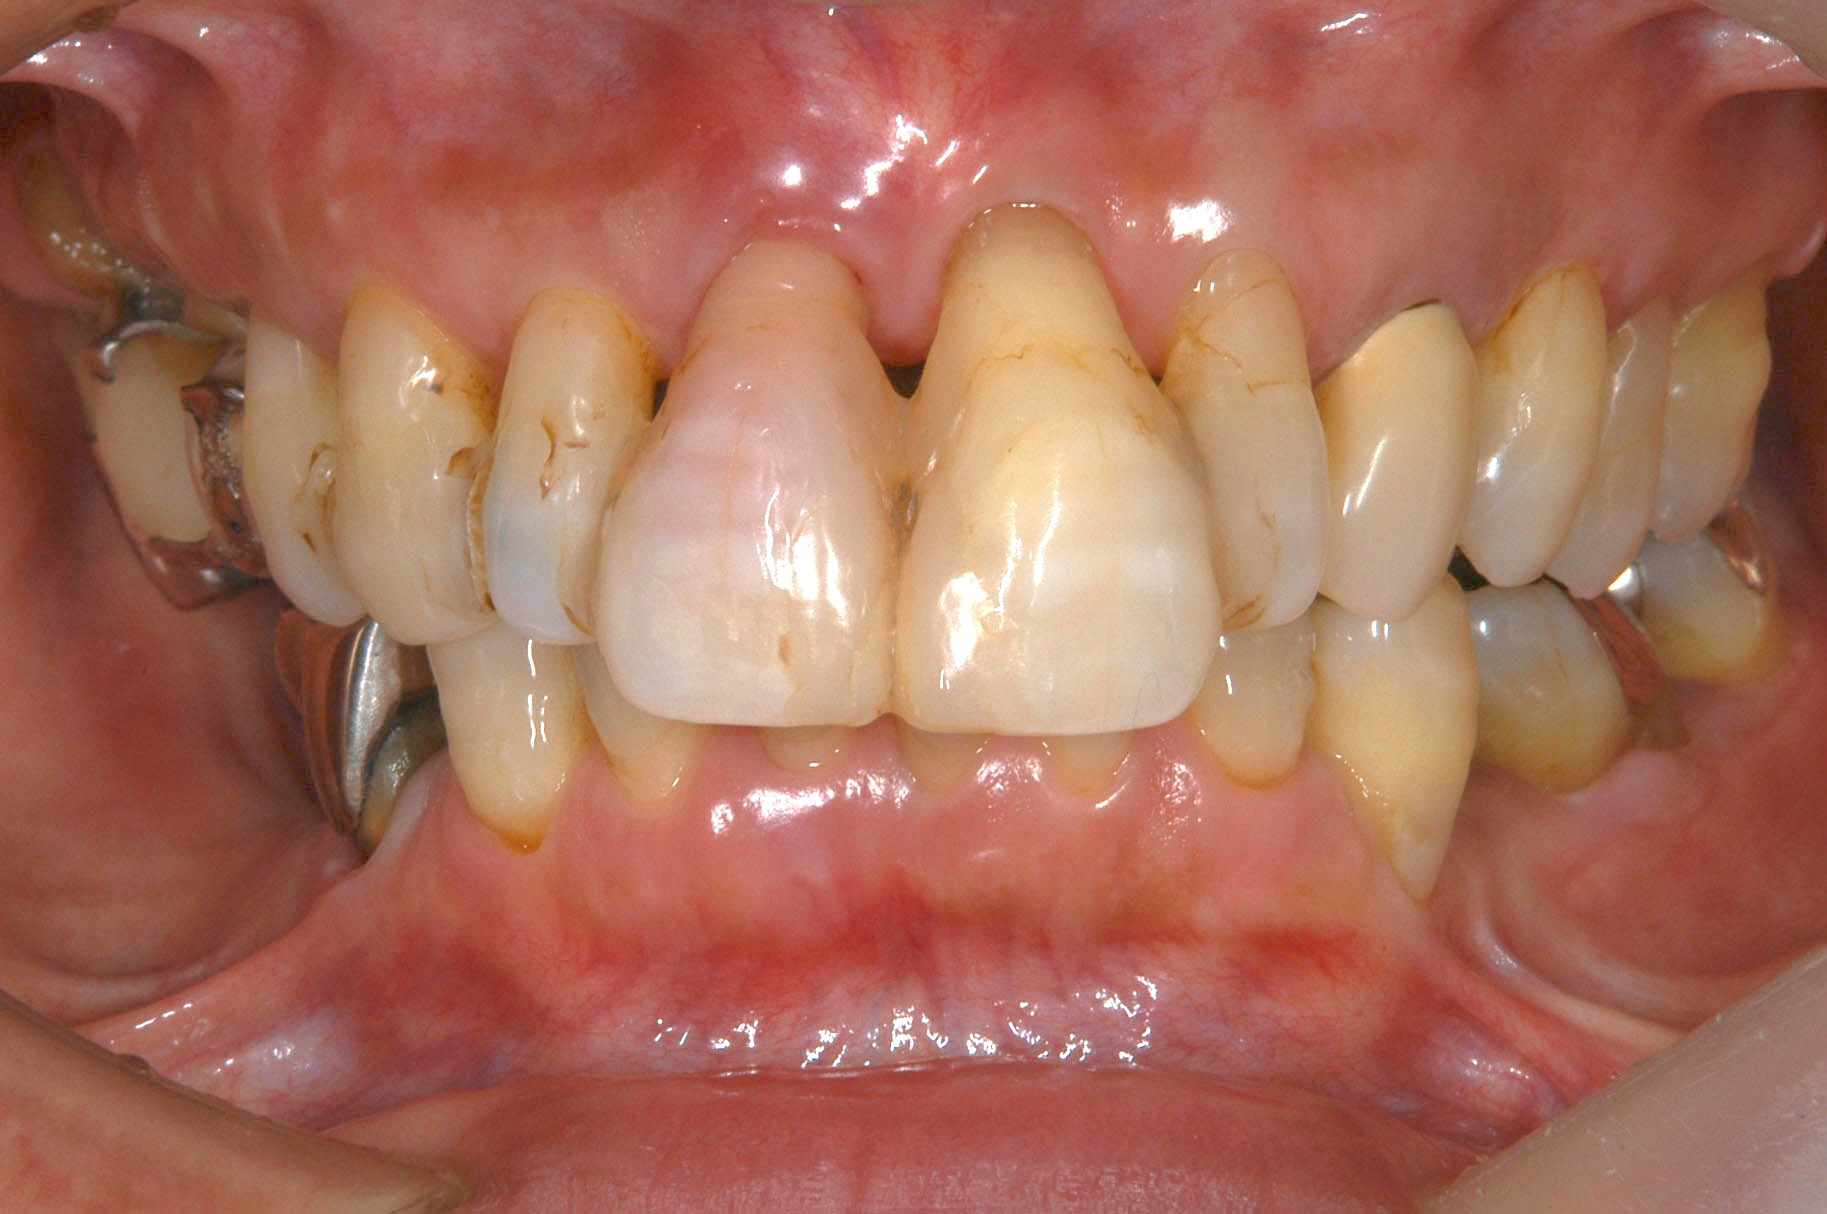

主な診断は、歯周病・虫歯・審美障害・不良補綴物・不正咬合・歯肉退縮です

初診